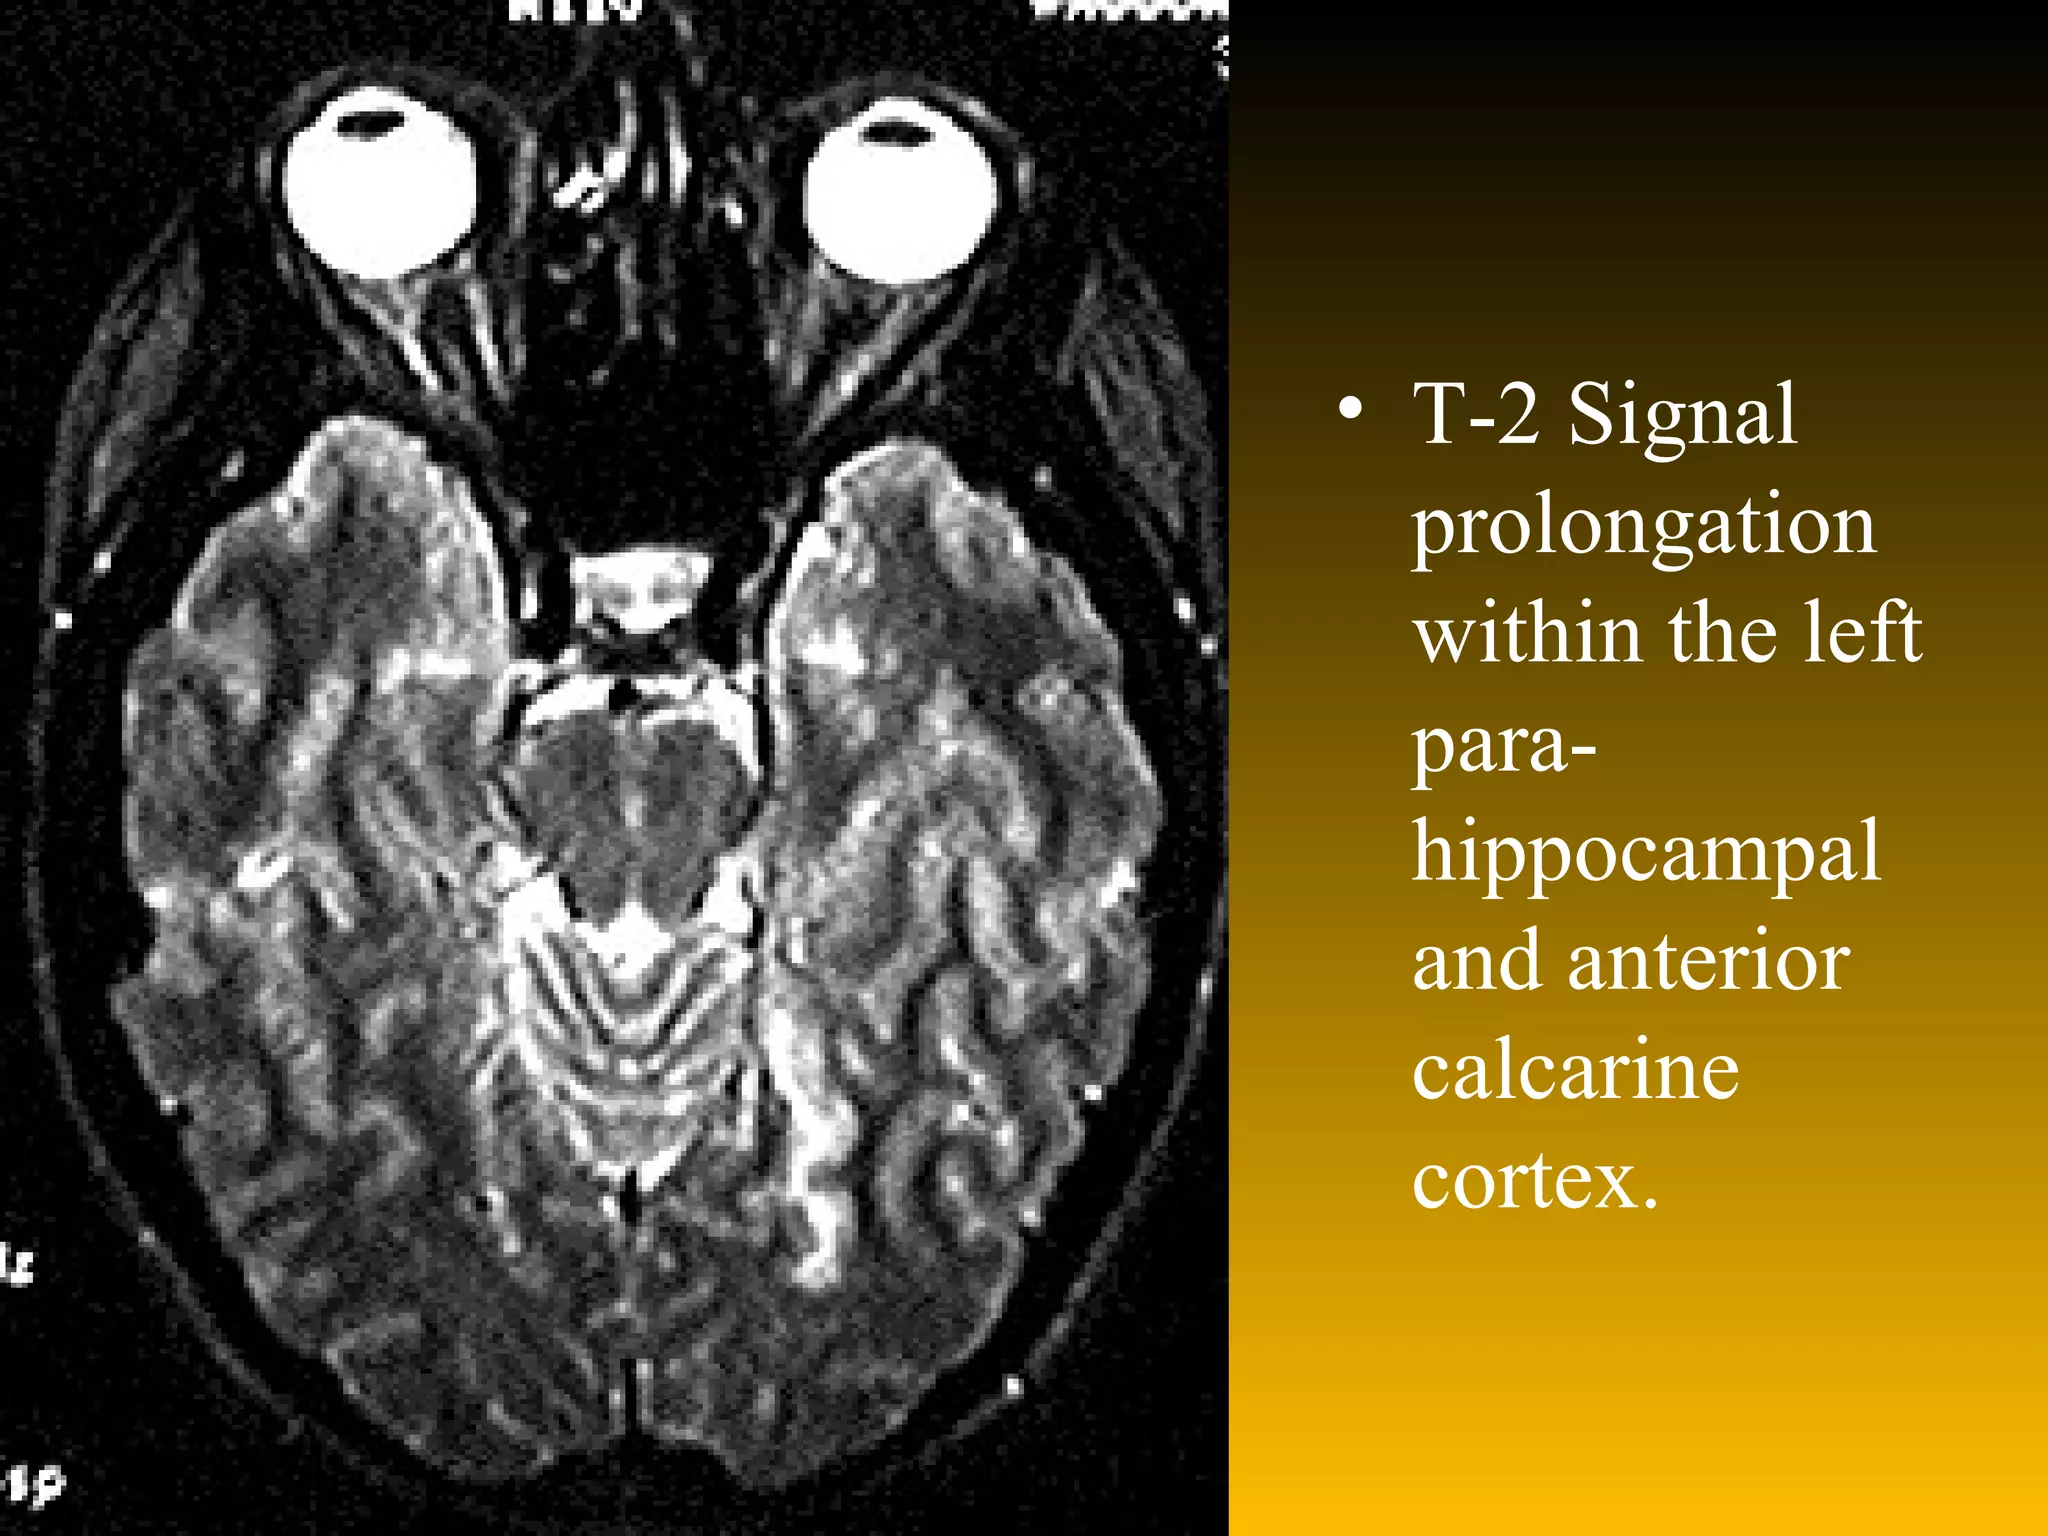

T-2 Signal prolongation within the left para-hippocampal and anterior calcarine cortex.

Discussion Case 96-2 represents a case of vertebral artery dissection with distal posterior circulation embolization and stroke. MRI scans revealed a right cerebellar hemisphere infarct (fig.1) and a mesial temporal infarct of the dominant hemisphere (fig 2). MRI of the neck with fat suppression reveals a classic cresentic lesion with signal characteristics of blood within the wall of the right vertebral artery (fig 3).

T-2 Signal prolongationwithin the left para-hippocampal and anterior calcarine cortex.

Discussion Case 96-2represents a case of vertebral artery dissection with distal posterior circulation embolization and stroke. MRI scans revealed a right cerebellar hemisphere infarct (fig.1) and a mesial temporal infarct of the dominant hemisphere (fig 2). MRI of the neck with fat suppression reveals a classic cresentic lesion with signal characteristics of blood within the wall of the right vertebral artery (fig 3).